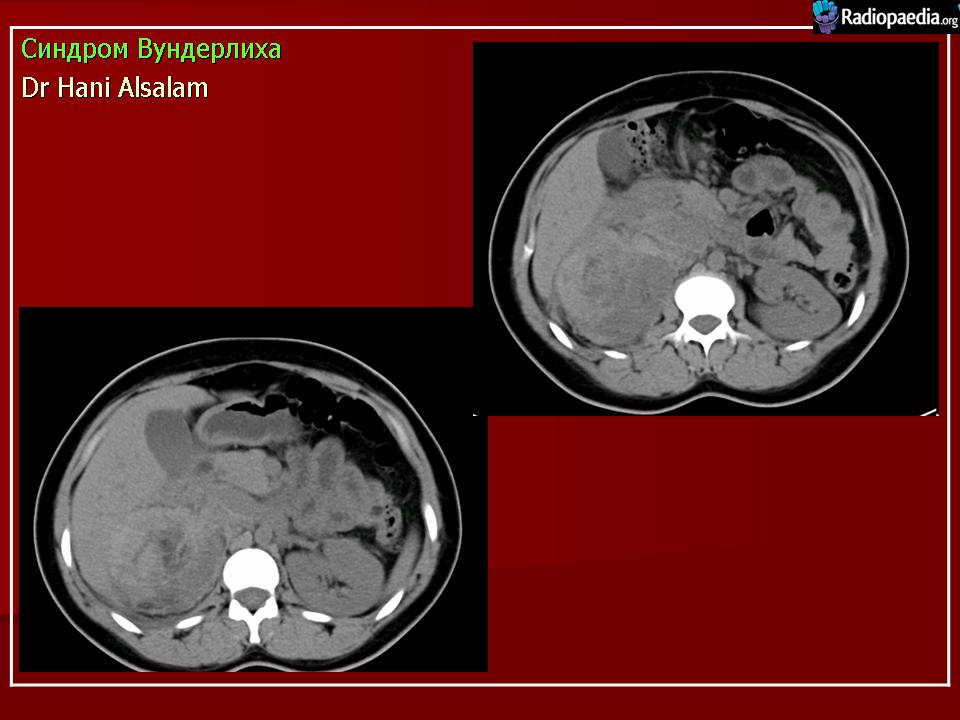

Вундерлих синдром - ndash; спонтанной, нетравматических почечной кровотечение ограничивается субкапсулярной и паранефральный пространстве. Это может быть первым проявлением почечной angiomyolipoma.

Синдром Вундерлиха. В русскоязычной литературе описывается как периренальная гематома, возникающая в результате сотрясения тела или удара в область почек (иначе говоря, травматического генеза). В англоязычной литературе описывается как нетравматическое кровоизлияние в подкапсульное или околопочечное пространство, часто как дебют ангиомиолипомы.